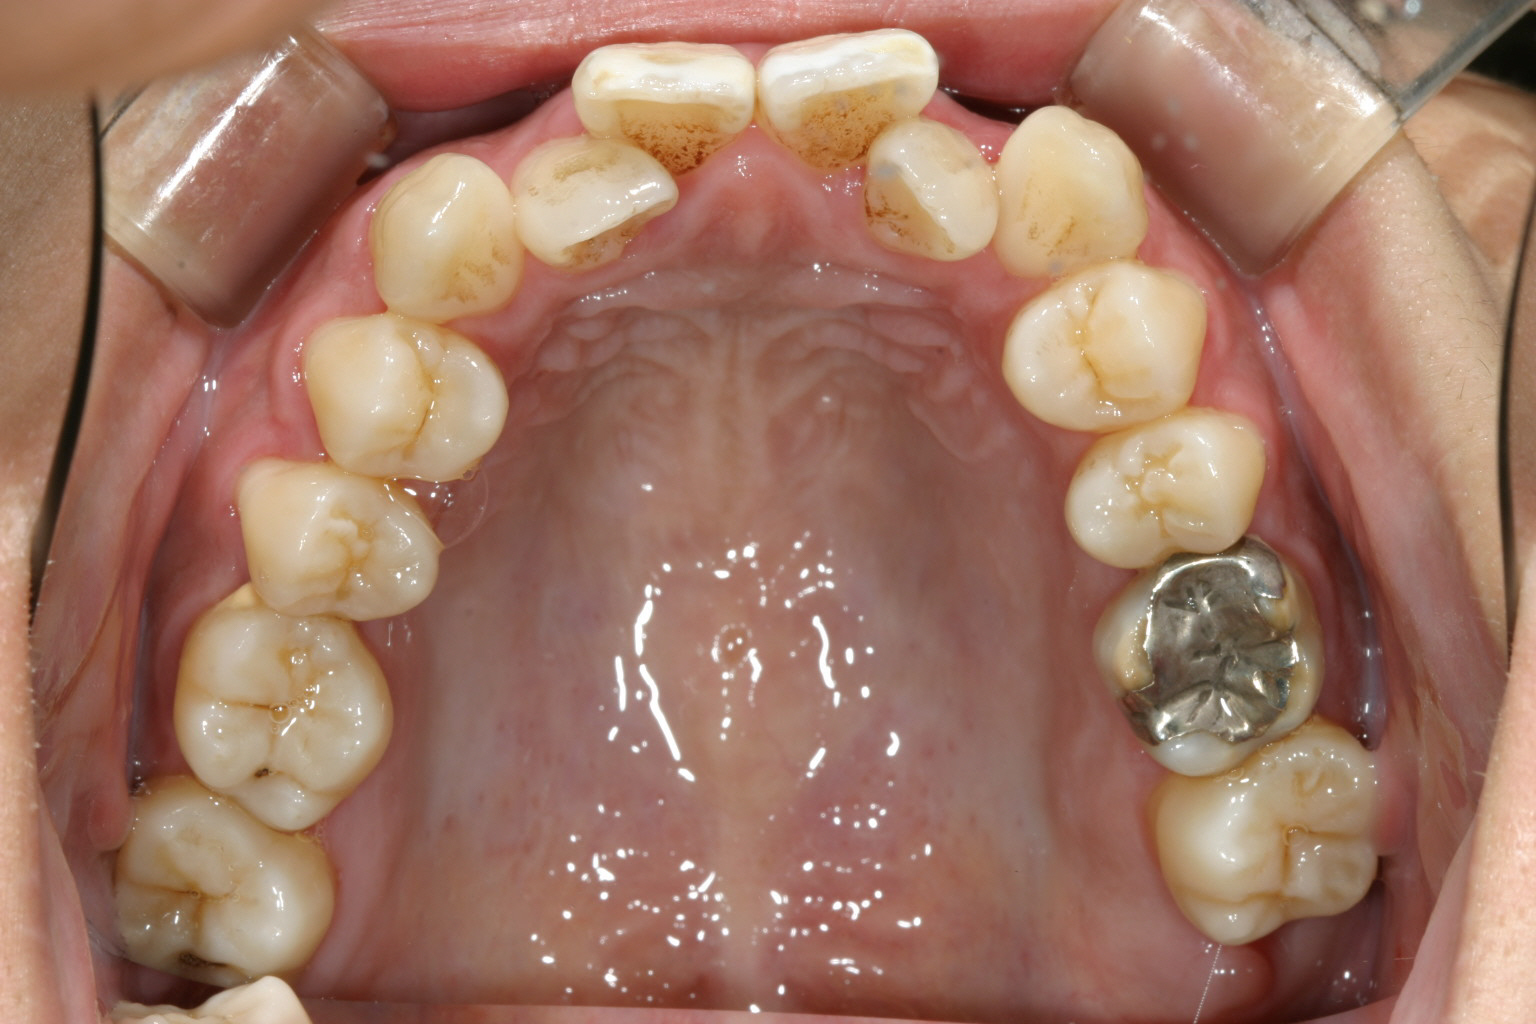

犬歯間が狭い為に上顎前歯が乱れています。

下顎の両側切歯が90度回転しています。 これが難儀なんです。 ワイヤーを留める為のブラケットを何度か貼りなおす必要が有ります。

上と下の歯が閉じず開咬状態です。